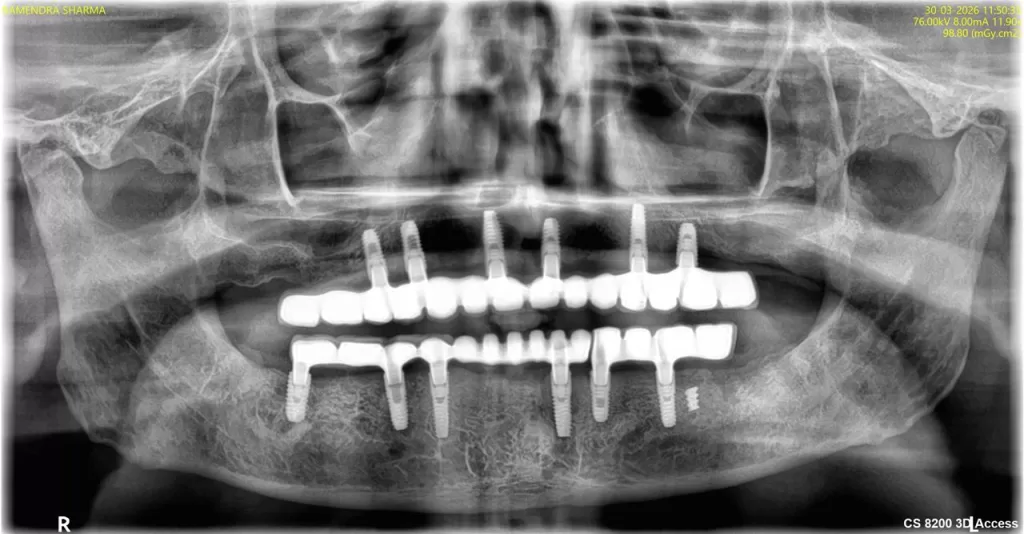

Dental Implants

A dental implant is an essentially an artificial tooth root which can support a crown, a bridge or a denture. The implant is made of titanium which will integrate with bone so that the implant then acts like a tooth root. Implants remove the need to wear part dentures and crowns and bridges made on top of implants will feel and resemble natural teeth.

- Consultation: You will meet with your dentist or oral surgeon to discuss your needs and expectations. They will also perform an examination to determine if you are a good candidate for dental implants.

- X-rays and other tests: Your dentist or oral surgeon may take X-rays and other tests to assess the condition of your jawbone and surrounding tissues.

- Bone grafting (if needed): If your jawbone is not strong enough to support an implant, your dentist or oral surgeon may recommend a bone graft. This involves taking bone from another part of your body and transplanting it into your jawbone.

- Implant placement: During implant placement surgery, your dentist or oral surgeon will make a small incision in your gum and drill a hole into your jawbone. The implant post will then be inserted into the hole and secured in place.

- Healing period: After implant placement surgery, you will need to wait several weeks or months for the implant to fuse with your jawbone. This process is called osseointegration.

- Abutment placement: Once the implant is fused with your jawbone, your dentist or oral surgeon will place an abutment on top of the implant. The abutment is a small metal post that will support your new tooth or teeth.

- Crown placement: Finally, your dentist will place a crown on top of the abutment. The crown is the artificial tooth that will replace your missing tooth.